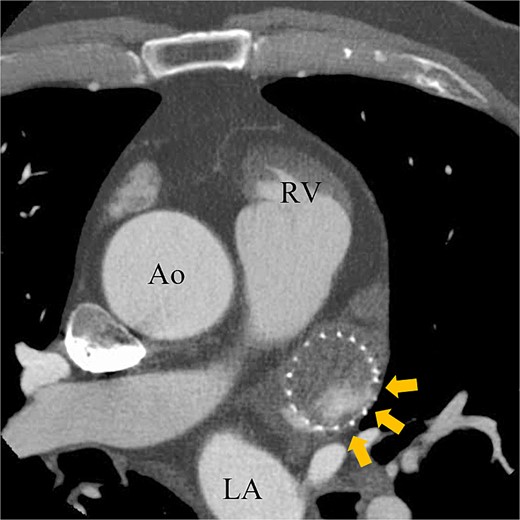

A 74-year-old male with a history of chronic atrial fibrillation (AF) for over 10 years, cardioembolic stroke, and cerebral hemorrhage, who had undergone LAA closure using the WATCHMAN device 1 year prior, was admitted after a follow-up contrast-enhanced CT scan revealed a 25-mm intracardiac mass in the right atrium (RA) (Fig. 1). After the WATCHMAN implantation, the patient was initially on direct oral anticoagulant (DOAC) but switched to dual antiplatelet therapy (DAPT) following the placement of a drug-eluting stent during percutaneous coronary intervention performed 9 months later. Transthoracic echocardiography revealed a left ventricular ejection fraction of 61% and a right atrial mass measuring 17 × 19 mm with slight mobility (Fig. 2). Despite anticoagulation therapy with heparin, the right atrial mass did not reduce in size. The patient decided to undertake surgical removal of the mass due to the potential risks of tumor or embolization. Additionally, contrast-enhanced CT showed a peri-device leak around the WATCHMAN device (Fig. 3). Considering the patient’s history of cerebral hemorrhage and the anticipated future cessation of anticoagulation therapy, we determined to perform WATCHMAN device explantation and LAA closure. Preoperative contrast-enhanced CT showed no thrombi attached to the WATCHMAN device and sufficient distance from the left circumflex artery (LCX) and the device (Fig. 4). We planned to remove the device by incising from the outside surface of the LAA. The Maze procedure was not performed because it was considered less effective due to the patient’s history of AF lasting more than 20 years and the presence of flat f-waves in lead V1 on the 12-lead electrocardiogram.

Preoperative enhanced computed tomography imaging showing peri-device leakage around the WATCHMAN (arrows). Ao, aorta.